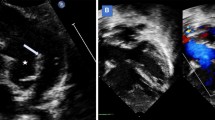

All patients underwent clinical assessment and transthoracic echocardiography (TTE) the day after the procedure. Chest radiographs (anteroposterior and lateral views) were also obtained before discharge three to five days after the procedure. Following hospital discharge, repeat radiography and TTE evaluations were scheduled after 1, 6, and 12 months, and then yearly after that. In addition, repeat catheterization was performed if the TTE indicated that the pressure gradient across the stent was 50% higher than that immediately after surgery.

Eighteen patients (51%) had repeat catheterization after a mean period of 3.6 ± 2.1 years after the initial implantation. Obvious side-branch vessel jailing or evidence of aneurysm formation was not identified, except for one patient with significant in-stent restenosis. During the follow-up, the stent’s minimal diameter did not differ from the diameter at implantation (follow-up: 8.5 ± 2.8 mm vs. initial: 8.9 ± 1.9 mm, P = 0.348, n = 18). However, the gradient in biventricular patients was slightly higher at the follow-up visit than initially (follow-up: 21.1 ± 18.1 mmHg vs. initial: 10.1 ± 10.4, P = 0.015, n = 14).

Ten patients underwent stent re-dilation (model S = 9, model M = 1) after a mean follow-up of 3.8 ± 2.0 years after implantation, improving the stent diameter from, on average, 7.0 ± 2.7 mm to 10.8 ± 1.6 mm (P < 0.001). Furthermore, in the biventricular patients (n = 7), the gradient pressure changed, on average, from 25.0 ± 18.3 mmHg to 7.3 ± 4.9 mmHg (P = 0.036). Repeat dilations were primarily indicated for arterial segments with a larger diameter or residual waist, except for one patient with an occlusive left pulmonary artery after the Glenn procedure; this patient had significant intimal proliferation and severe in-stent stenosis at the 1-year follow-up. Furthermore, despite receiving aspirin and warfarin after the initial procedure and a successful re-dilation, the stent became obstructed again, but a third intervention was abandoned. Stent fractures or migrations were not observed on further dilation (Fig. 3).